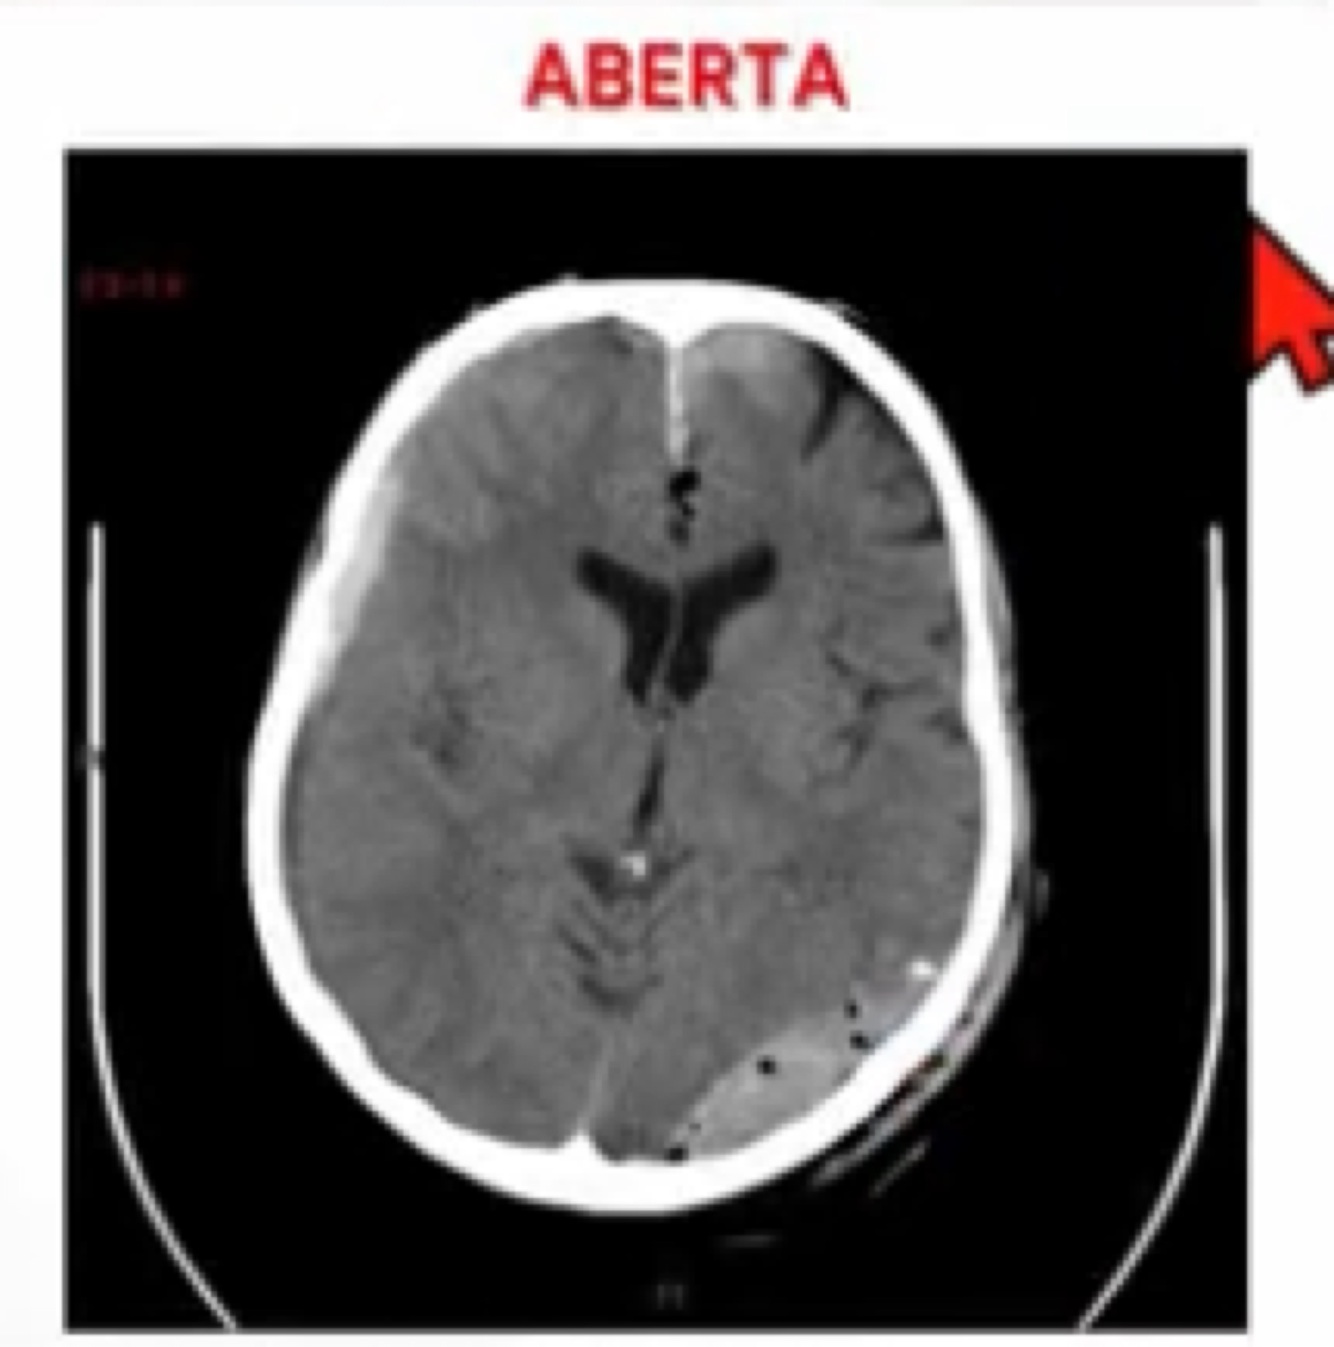

Q

Qual o tipo de fratura a seguir?

A

Aberta.

As bolhas de ar indicam pneumoencéfalo.